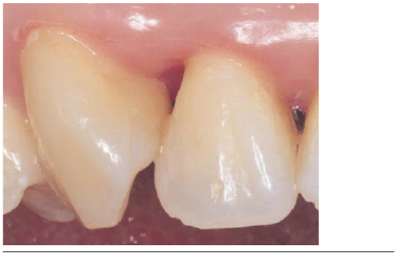

Se evaluó a los 60 días post-aplicación, observándose clínicamente aumento de volumen en sentido vertical y horizontal de las papilas (Figuras 3 y 4), mejorías en los parámetros estéticos y ausencia de signos clínicos de inflamación.

Se clasificaron los resultados en: triángulo negro cubierto totalmente y triángulo negro cubierto parcialmente. Además se graficó en una tabla la cantidad de milímetros ganados en cada papila. (Tabla 2).